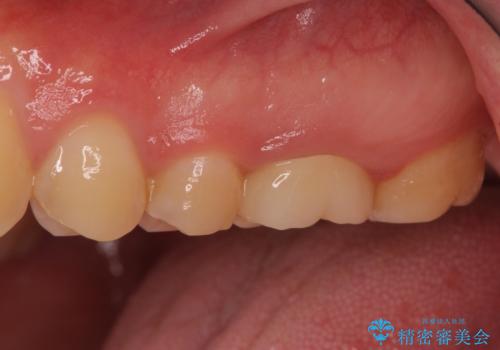

根管治療を実施した後、フルジルコニアクラウンに補綴することとしました。

前医での処置後、治療前には気にならなかった痛み続いていたようですが、当院での処置後は痛みが徐々に引いていき、治療から半年が経過した時点では全く違和感も感じなくなりました。

根管治療後のクラウンも、まるでもとの自分の歯のように自然な仕上がりとなり、患者様には大変満足していただけました。